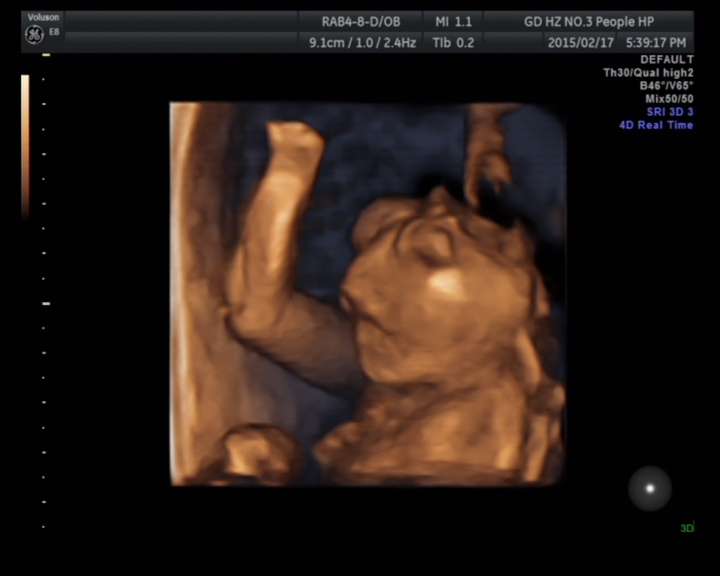

故事發(fā)生于2015217號(年廿九)下午,一對年輕的夫婦滿臉笑容地向超聲科走來,準(zhǔn)媽媽懷孕約21周,來醫(yī)院做胎兒彩超檢查,想著明天回家開開心心過新年。誰知道天有不測風(fēng)云,張春云副主任醫(yī)師在檢查中發(fā)現(xiàn)胎兒患有先天性畸形——無腦兒、復(fù)雜性心臟畸形、唇腭裂。就在那一瞬間,一切都變了,她哭了,他也變得心情沉重,臉上也失去了笑容。

無腦畸形是指胎兒顱蓋骨缺失。具體病因不明,可能與脊柱裂相似,也是多因素致病,包括遺傳、環(huán)境、致畸因子如射線、水楊酸鹽、磺胺等。無腦兒表現(xiàn)為無顱蓋、無大腦,僅見顱底或顱底部分腦組織,雙眼眶位于最高處,無額骨顯示,呈“青蛙”狀面容。無腦兒一般不能存活,少數(shù)生出來后能存活幾個小時或一天。因此,一旦超聲明確診斷,將立即終止妊娠。